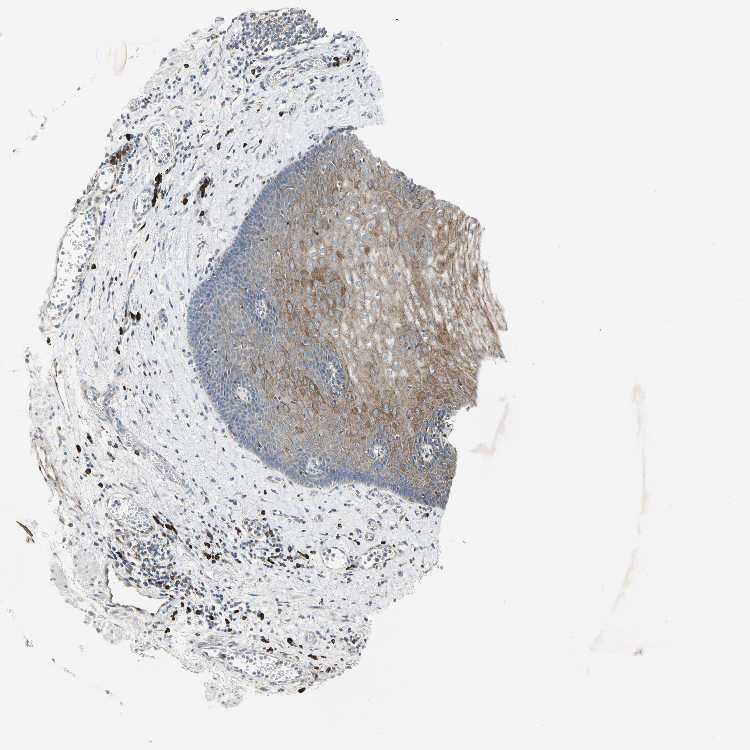

ESOPHAGUS - Antibody stainingi

Antibody staining in the annotated cell types in the current human tissue is reported as not detected, low, medium, or high, based on conventional immunohistochemistry profiling in selected tissues. This score is based on the combination of the staining intensity and fraction of stained cells.

Each image is clickable and will lead to virtual microscopy that enables deeper exploration of all samples and also displays staining intensity scores, fraction scores and subcellular localization as well as patient and tissue information for each sample.

Antibody HPA005445

Squamous epithelial cells Medium